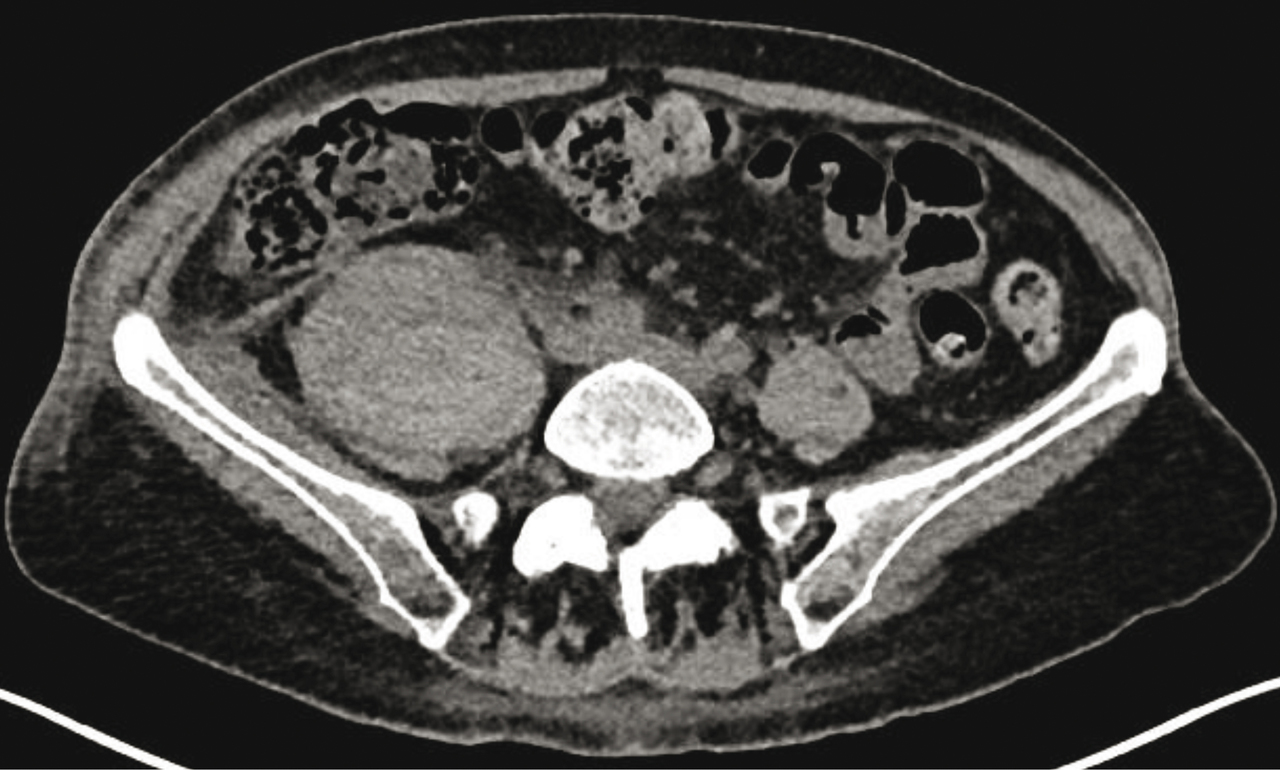

La bonne réponse est : hématome du psoas. L'hématome du psoas est une complication connue des traitements anti-coagulants ou des troubles de l'hémostase tels que l'hémophilie. Il doit être recherché devant une cruralgie, un psoïtis, voire un déficit neurologique sensitif et/ou moteur (compression du nerf fémoral). Le scanner met en évidence une augmentation de la taille du psoas, avec une masse plus ou moins collectée, spontanément hyperdense, à la phase aiguë. En cas de doute sur un abcès ou une tumeur, une IRM est réalisée.